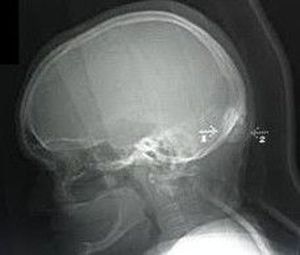

Dx?

Osteoma (benign)of the occipital bone

Some tumour on the occipital bone???

Osteoma of occipital region